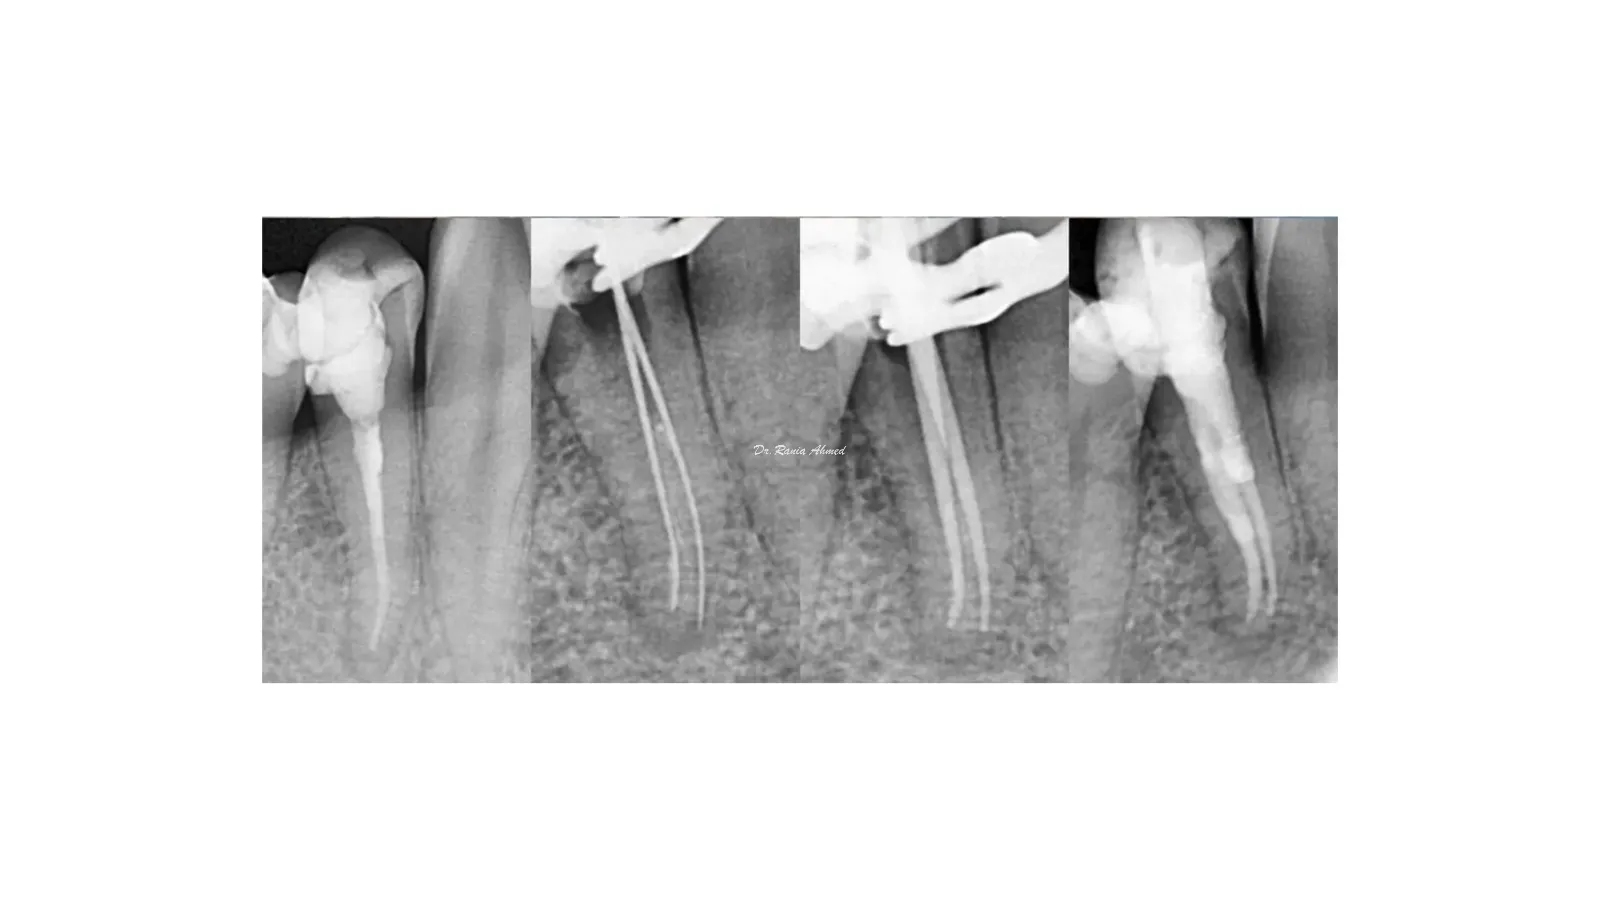

Endodontic Treatment